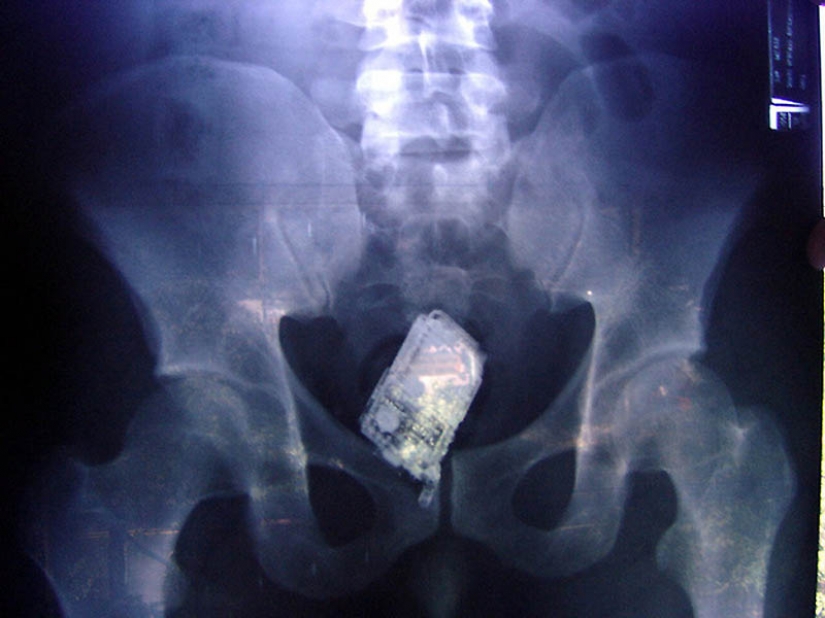

14. De células en el intestino de los prisioneros.